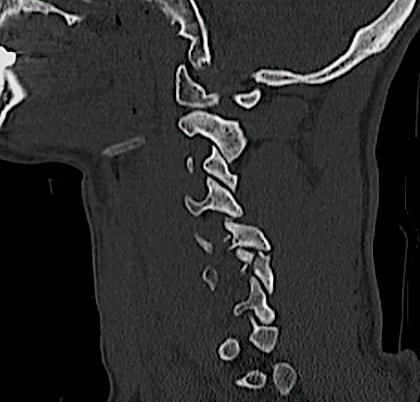

Obsérvese el hematoma prevertebral, la cifosis segmentaria y la afectación vertebral C4, C6 y C7.

El paciente presentaba tetraplejia nivel C4.

Los cortes sagitales demostraban una subluxación inestable en C4-C5 además del compromiso anterior C6-C7.